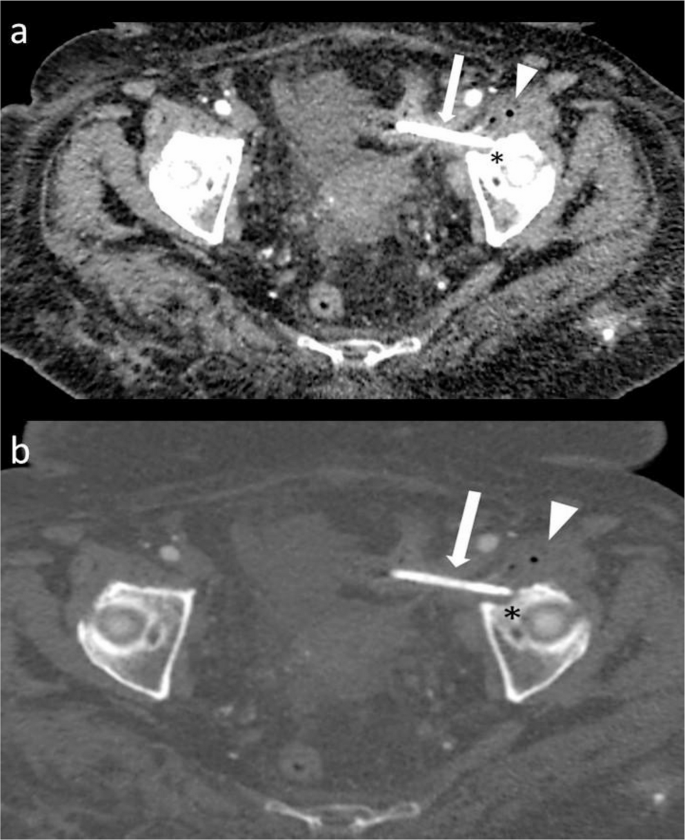

影像学检查显示,一根弯曲的胆道支架从盆腔中部延伸至左下腹,经过髂耻线和髂坐线。即使在单投影X光片上,也能清晰看到支架的远端外侧末端,其末端终止于左髋臼顶部。支架周围局部骨溶解变化表明支架与骨骼有直接接触。X光片未显示髋关节周围有渗出、皮质边界模糊或硬化现象(图1)。增强腹部和盆腔CT显示支架正确放置在胆总管内,而另一根支架则移位至乙状结肠。移位的支架部分位于结肠腔内,其余部分穿透了结肠壁,穿过脂肪层、左髂腰肌筋膜和髂肌,越过髂骨的弓状线,导致髋臼前部出现局部骨质侵蚀,边缘清晰,轮廓平滑(图2)。在支架附近的小范围内观察到单层线性骨膜反应(图2)。在更外围的区域,髂骨上观察到向髋臼前部延伸的硬化改变,以及皮质不规则和小的硬化边缘的侵蚀灶(图3)。

图3

这是盆腔的轴向增强CT图像(软组织窗)和骨窗)。可见一根胆道支架穿透了乙状结肠壁(箭头所示),形成了左髂腰肌脓肿(箭头所示),以及髋臼的局部侵蚀(*)。在髂骨上观察到向髋臼前部延伸的硬化改变,以及皮质不规则和小的硬化边缘的侵蚀灶

在移位支架的位置,发现髂腰肌内有一个38 × 25 mm的多房脓肿,壁厚,含有多个气体灶,并显示周围对比增强。脓肿紧邻髂骨皮质,皮质基本完整,未见皮质破坏,向下延伸至髂腰肌囊(图3b和4)。乙状结肠的穿孔壁和盆腔的侧壁在左外髂动脉和静脉后方粘连。移位的支架在这两个结构之间形成了一个薄薄的瘘管,穿孔为自限性。由于她患有充血性心力衰竭,因此出现了肝周、脾周和盆腔积液,这些积液是她全身疼痛的主要原因。多学科团队(包括传染病科、骨科和普通外科)认为,鉴于患者没有急性腹膜炎、穿孔为自限性以及存在合并症,无需进行手术干预。针对脓肿问题咨询了介入放射科专家,但由于病灶位置和患者合并症的情况,未进行脓肿引流。对于左髋部和左腿疼痛,采取了观察性治疗策略,首先治疗腹部病变,观察炎症控制后的疼痛是否缓解。采用保守治疗,包括经验性抗生素(阿莫西林克拉维酸钾3 × 1 g,每日口服3次,环丙沙星2 × 500 mg,每日口服2次,持续6周)和止痛治疗(必要时口服萘普生钠)。最终决定通过直肠乙状结肠镜取出支架,该手术也证实了我们的诊断。